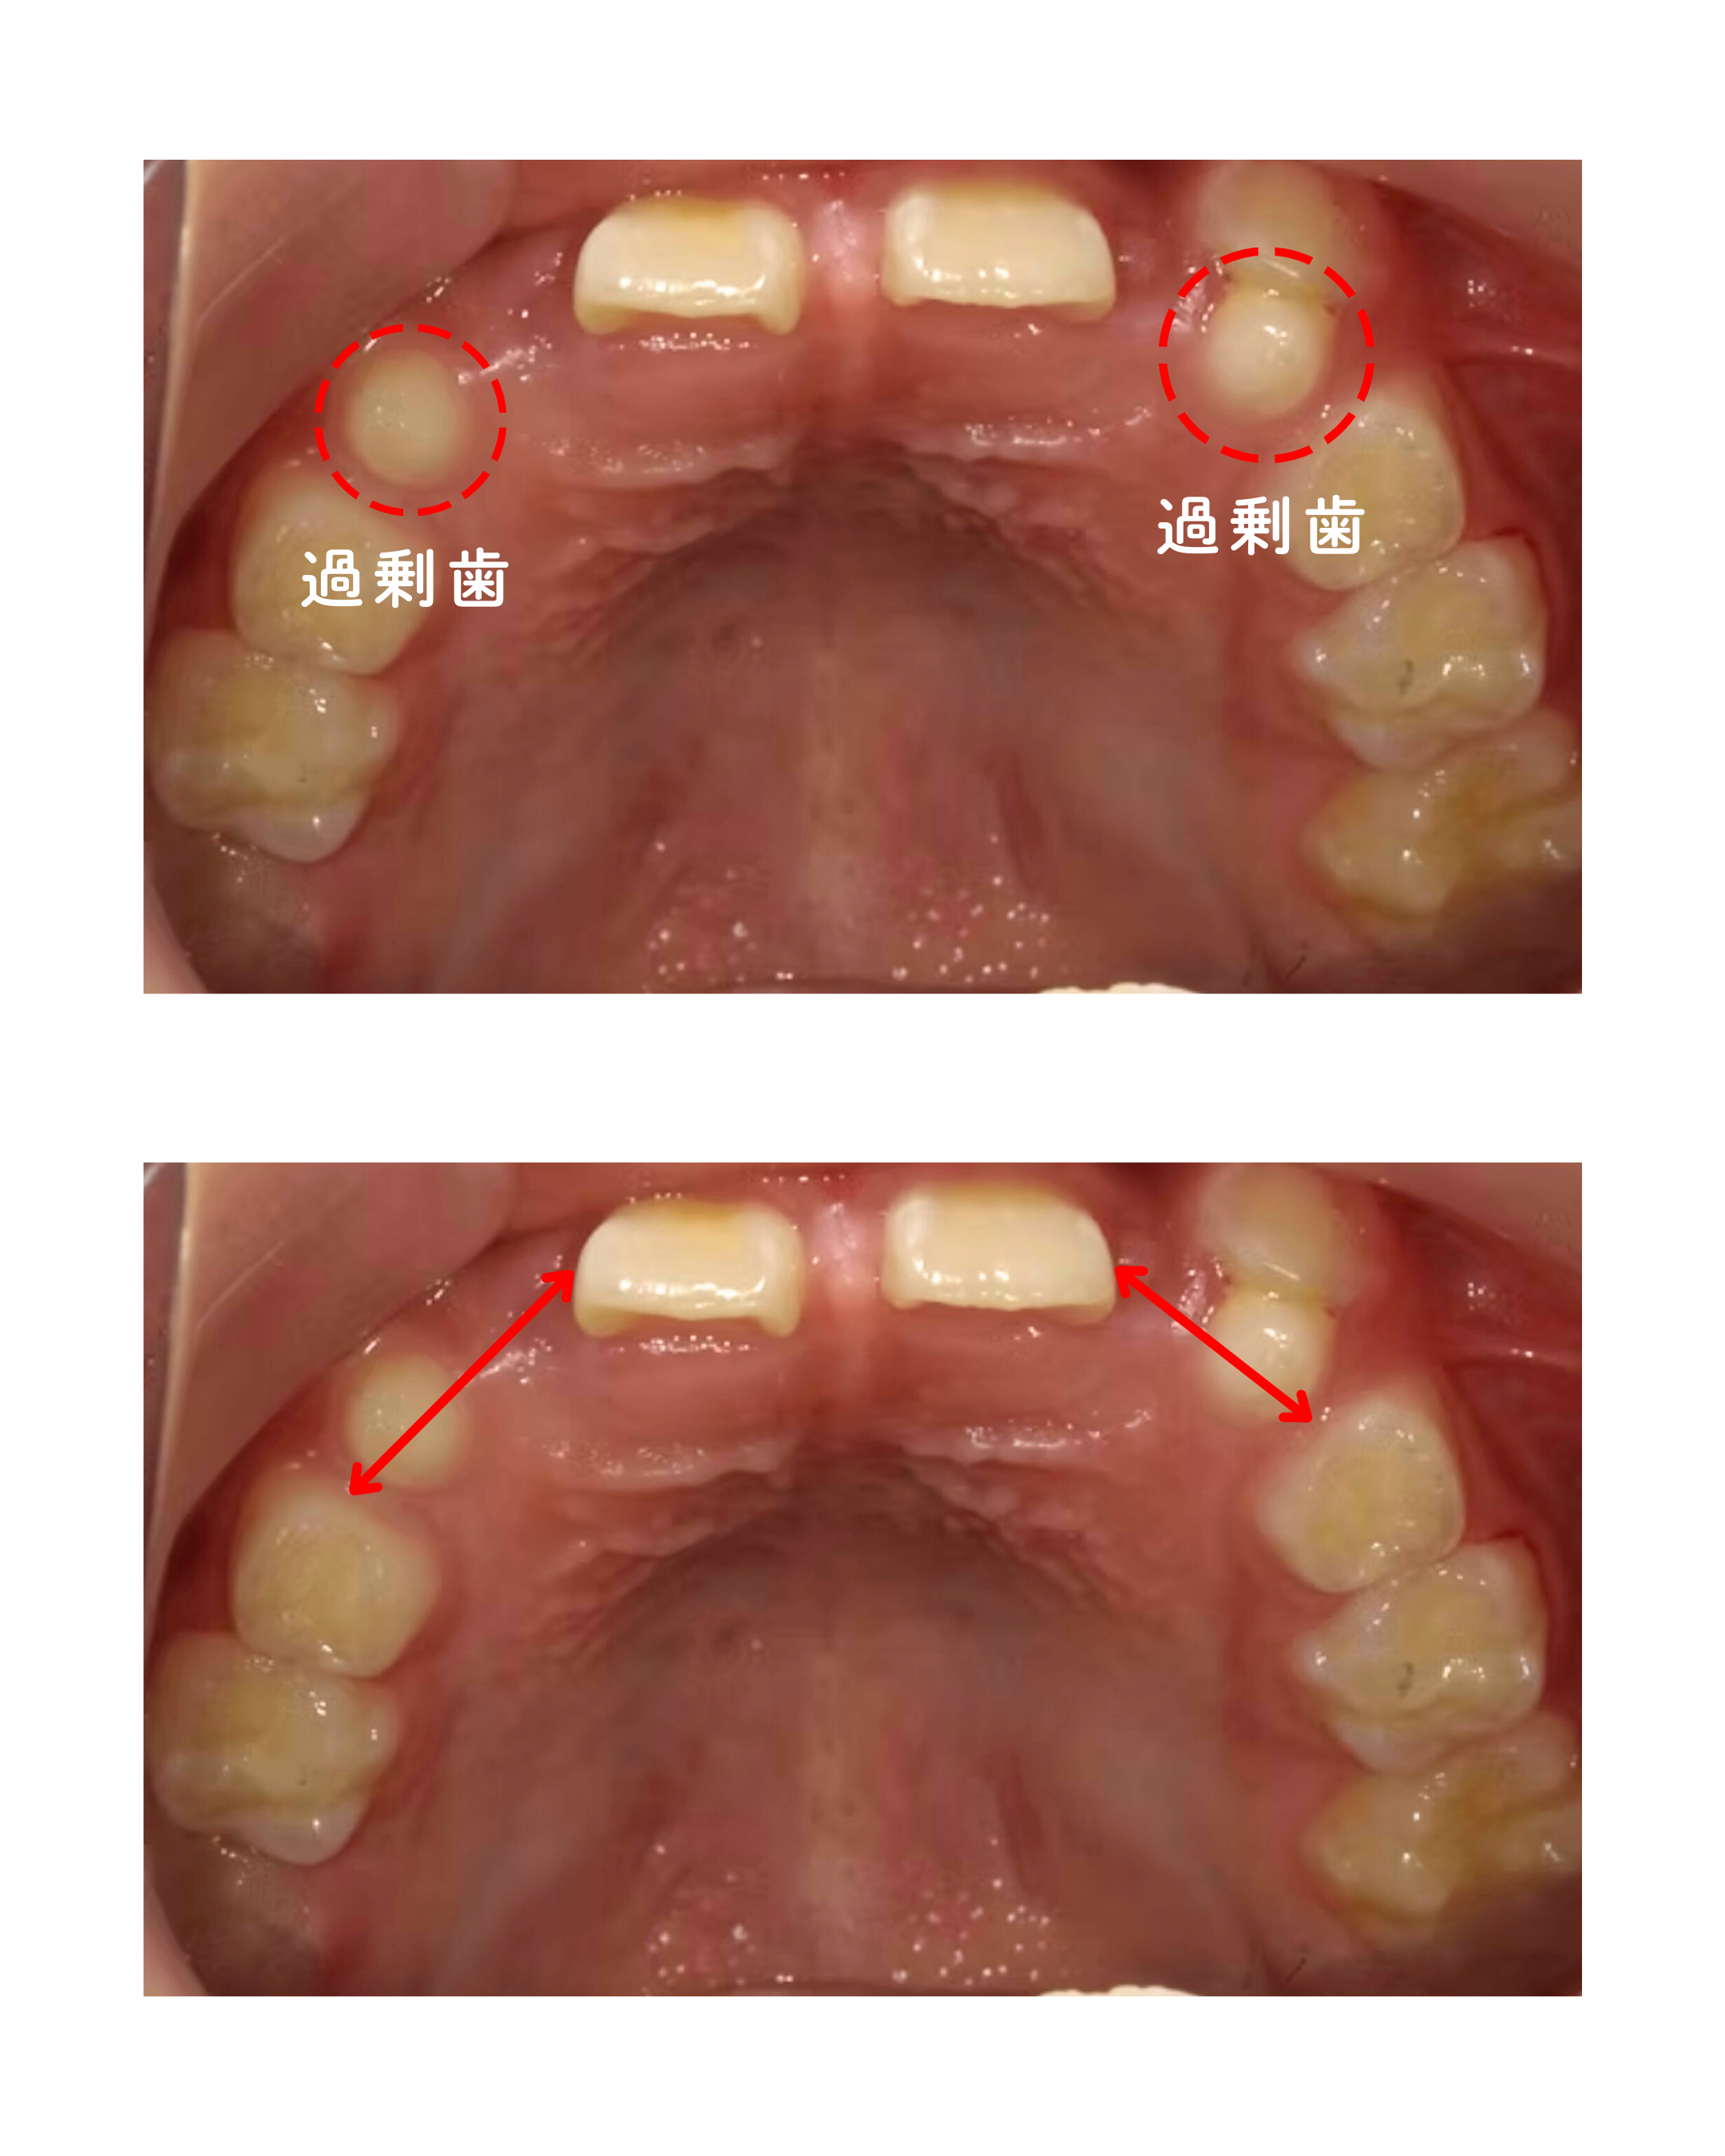

「上アゴの状態について」

本来、前歯が生えてくるべきスペースには過剰歯があり、さらに上アゴ自体が小さいため、↔のスペースに永久歯が2本ずつ生えてくるがスペースがありませんでした。

そのため、まずは「上アゴを拡げて十分なスペースをつくる」ことが治療のポイントとなりました。